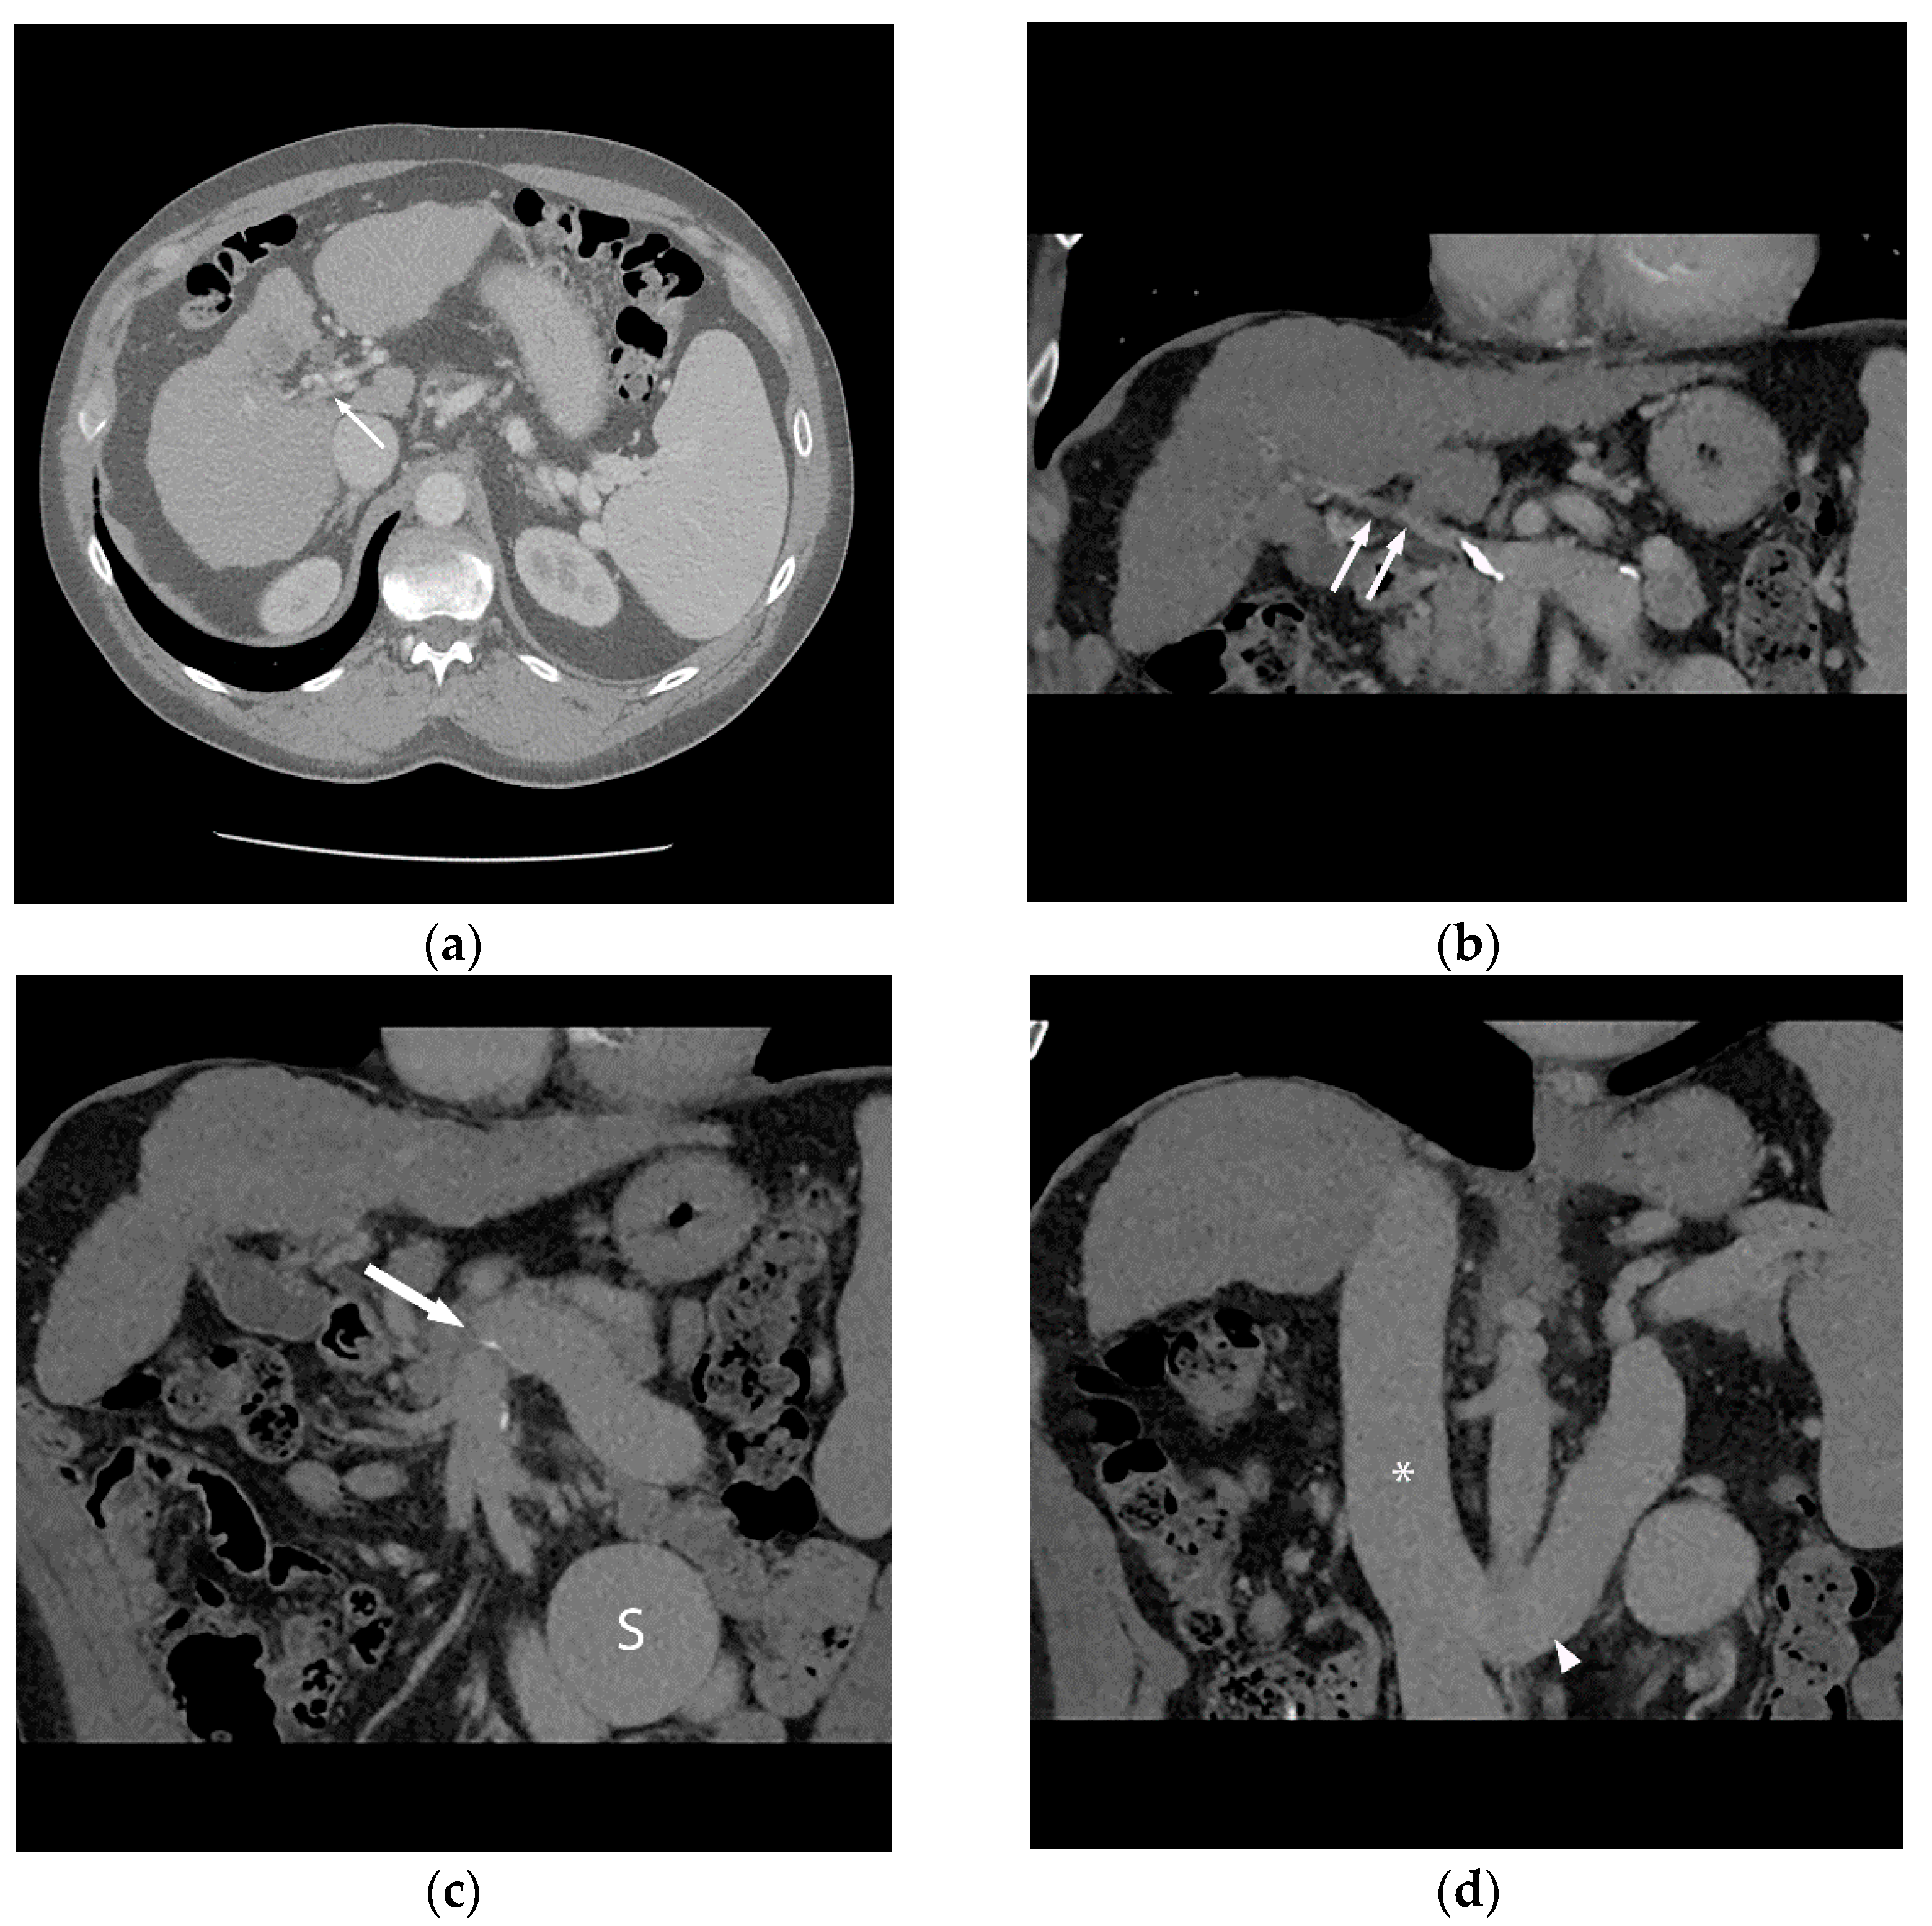

Figure 3.

Coronal non-contrast CT (a) performed two days later (same patient as Figure 1 and Figure 2) demonstrates a larger-caliber portal vein (white arrow). The caudal aspect of the TIPS is noted (black arrow). The patient underwent successful orthotopic liver transplant approximately 1 year later (b), and remains well after 53 months of follow-up.